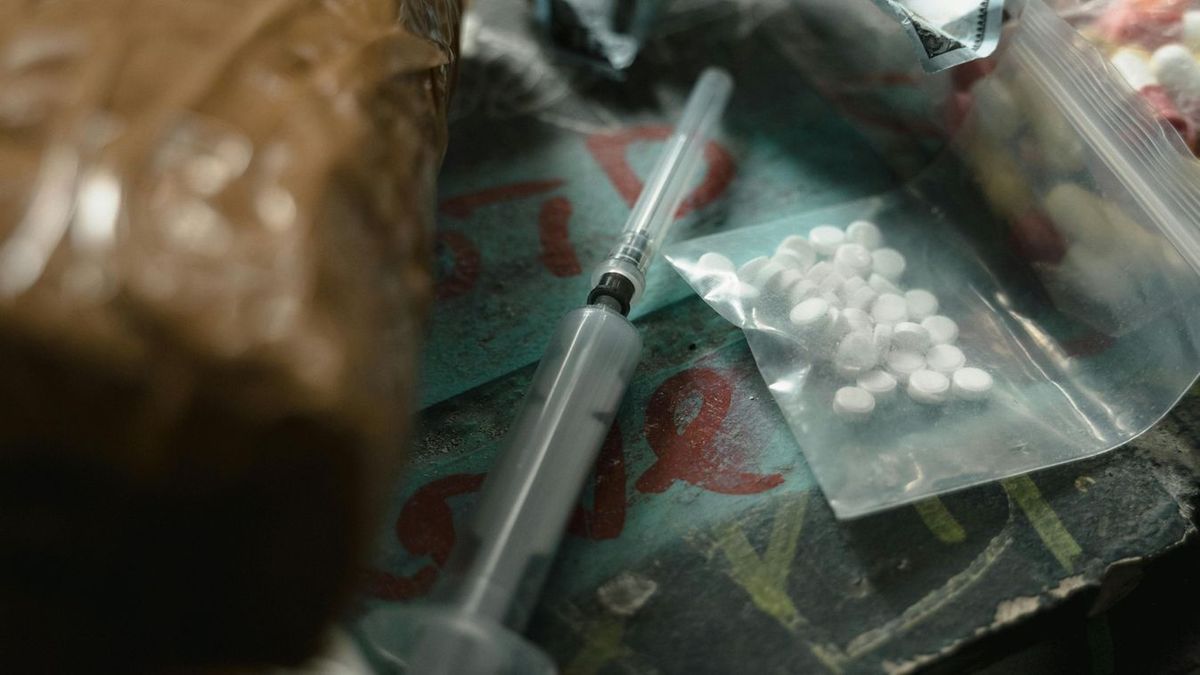

Durva következményekkel jár, ha egy várandós nő drogozik

A drogfüggőség rendkívüli hatással van a magzat fejlődésére is.